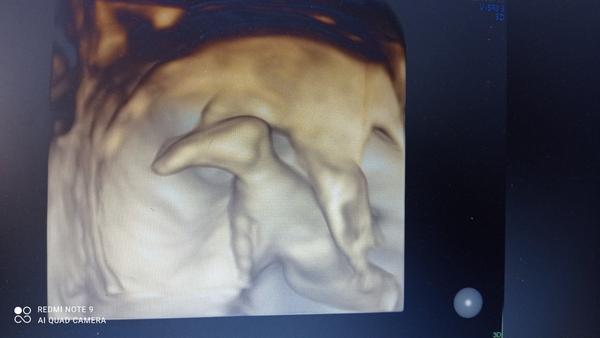

@22stanka22 ahoj... Ja idem na vklad..